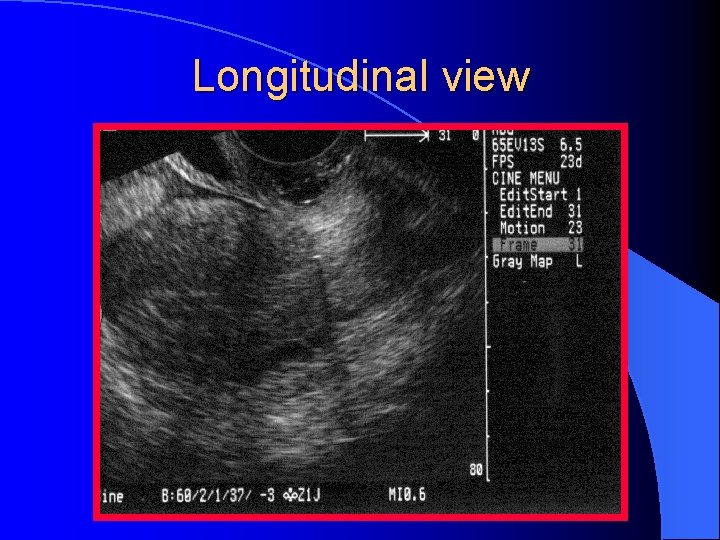

Longitudinal view